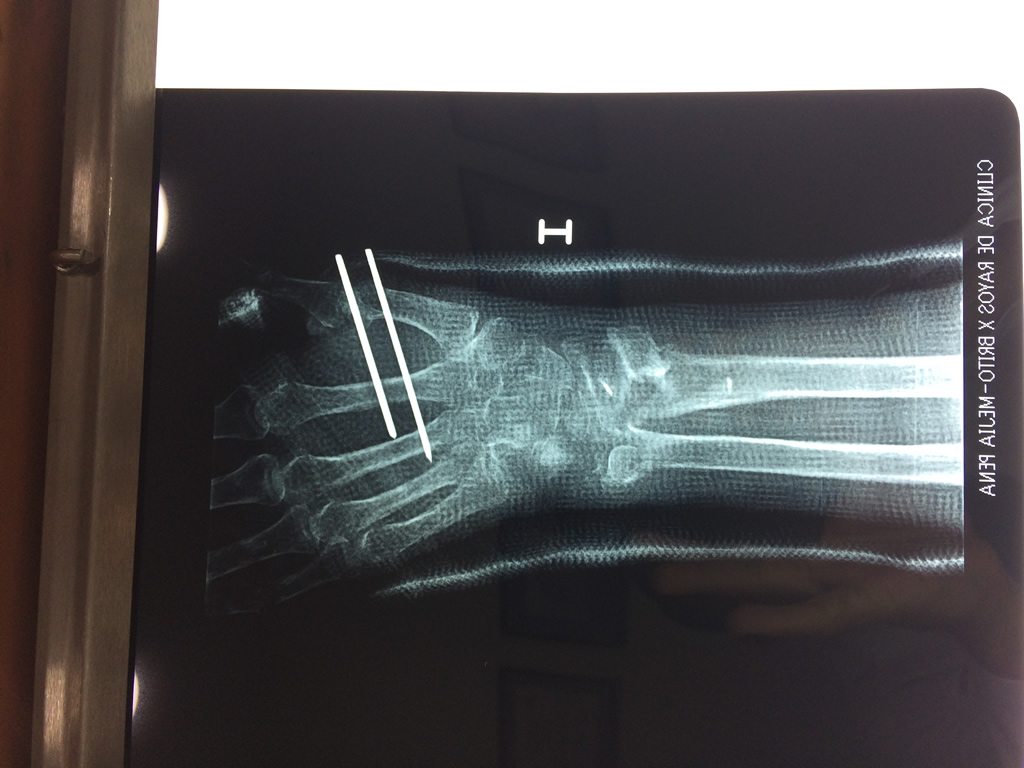

Húmero - Cirugías de Muñecas y Manos

Los procedimientos más comunes en cirugía de la mano son aquellos destinados a reparar traumatismos, incluyendo lesiones de tendones, nervios, vasos sanguíneos, y articulaciones; huesos fracturados; y quemaduras, cortes, y otros daños de la piel.